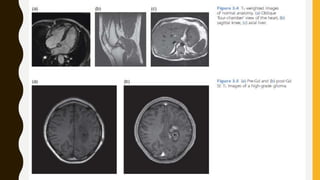

Introduction to the T-Words:

T2-Weighted Images

T2-weighted (T2w) images are one of the most important MR images, because they are

sensitive to fluid collections.

Since many pathological tissues have high capillary density, or excess fluid

accumulations, these images provide confirmation of the preliminary diagnosis and

the extent of the disease.

So, for example, the meniscal tear in the knee shows up well because the synovial fluid

in the tear is brighter than the cartilage.

• T1-Weighted Images

– T1-weighted (T1w) images can be produced using either SE or GE sequences. Unlike T2w

images, where long T2 tissues have a bright signal, on T1w images the longest T1s have the

darkest signal. Tissues with short T1s appear brighter. T1w images are usually quite fast to

acquire, because they have short repetition times (TR). T1w images often have excellent

contrast: static fluids, e.g. synovial fluid, are very dark, water-based tissues are mid-grey

and fat-based tissues are very bright. The appearance of flowing fluids (e.g. blood) depends

on the speed of flow and the sequence parameters. T1w images are often known as

‘anatomy scans’, as they show most clearly the boundaries between different tissues.